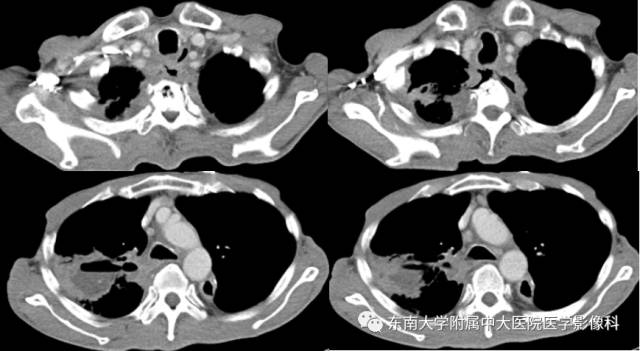

男,60岁,因“食管癌术后5年余,进食呛咳10天”入院。

影像学表现